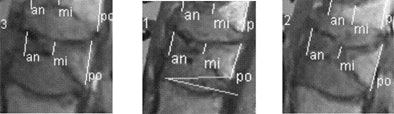

| Preoperative MRI (above) and postoperative CT (below) show growth in vertebral height before and after vertebroplasty, measured at anterior border (an), medial (mi), and posterior border (po) of the vertebral body at right (image at left), middle (middle), and left (image at right) for both modalities. Compared to control subjects, postprocedural mean height of treated vertebrae increased significantly (p < 0.001) from 4% to 38% of initial height, after vertebroplasty for an overall increase of 0.1-1.5 cm, median value 0.16-0.27 cm. All images courtesy of Dr. Johannes Hierholzer. |